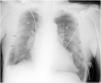

This is the case of an 86-year-old man admitted to our unit after emergency percutaneous coronary intervention due to anterior ST-segment elevation acute myocardial infarction with implantation of 2 drug-eluting stents into the LAD and first diagonal branch. Upon admission the situation of the patient remains hemodynamically and respiratory stable with 93% oxygen saturation on pulse oximetry without oxygen supply. A thoracic x-ray (Rx) is performed in the supine position that reveals the presence of 2 lines suggestive of bilateral pneumothorax (Fig. 1, arrows) that cannot be seen in the upper lobes (Fig. 1, arrowheads). To rule out the presence of bilateral pneumothorax, a bilateral thoracic ultrasound is performed that reveals the presence of pleural «sliding» on the imaging in M-mode or «seashore sign» (Fig. 2). In an Rx performed afterwards while in the semi-sitting position, only a small right baseline line can be seen (Fig. 3), and diagnosis of false bilateral skin fold pneumothorax is achieved.